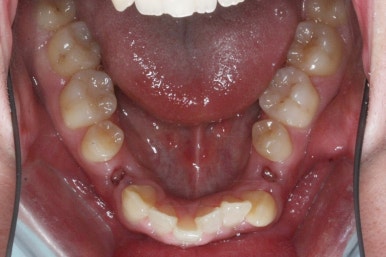

치료 전과 가장 최근의 사진을 비교해 보겠습니다.

좌측이 부산구순구개열 전, 우측이 가장 최근의 사진들입니다.

거꾸로 물리던 앞니가 개선되었습니다.

좁아져 있고 찌그러진 위턱뼈의 형태가 개선되었습니다.

영구치 개수가 모자라는 선천결손이 있었지만 아랫니도 개수를 맞춰줌으로써 치아의 맞물림도 상당히 좋아졌습니다.